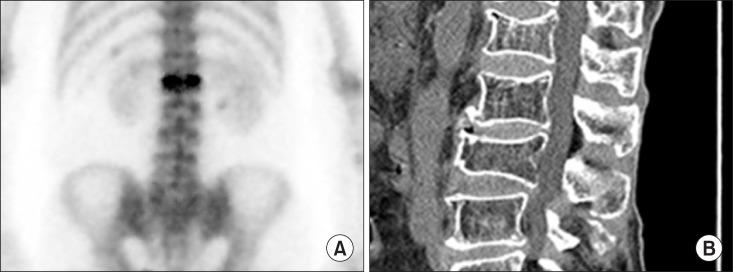

Nuclear medicine imaging is widely used in pain medicine. Low back pain is commonly encountered by physicians, with its prevalence from 49% to 70%. Computed tomography (CT) or magnetic resonance imaging (MRI) are usually used to evaluate the cause of low back pain, however, these findings from these scans could also be observed in asymptomatic patients. Bone scintigraphy has an additional value in patients with low back pain. Complex regional pain syndrome (CRPS) is defined as a painful disorder of the extremities, which is characterized by sensory, autonomic, vasomotor, and trophic disturbances. To assist the diagnosis of CRPS, three-phase bone scintigraphy is thought to be superior compared to other modalities, and could be used to rule out CRPS due to its high specificity. Studies regarding the effect of bone scintigraphy in patients with extremity pain have not been widely conducted. Ultrasound, CT and MRI are widely used imaging modalities for evaluating extremity pain. However, SPECT/CT has an additional role in assessing pain in the extremities.

核医学成像在疼痛医学中被广泛应用。腰痛是医生常见的病症,其患病率在49%至70%之间。计算机断层扫描(CT)或磁共振成像(MRI)通常用于评估腰痛的病因,然而,这些扫描结果在无症状患者中也可能出现。骨闪烁显像在腰痛患者中具有额外的价值。复杂性区域疼痛综合征(CRPS)被定义为一种四肢疼痛性疾病,其特征为感觉、自主神经、血管舒缩和营养障碍。为协助CRPS的诊断,三相骨闪烁显像被认为比其他检查方法更具优势,并且因其高特异性可用于排除CRPS。关于骨闪烁显像对四肢疼痛患者影响的研究尚未广泛开展。超声、CT和MRI是评估四肢疼痛广泛使用的成像方式。然而,SPECT/CT在评估四肢疼痛方面具有额外作用。